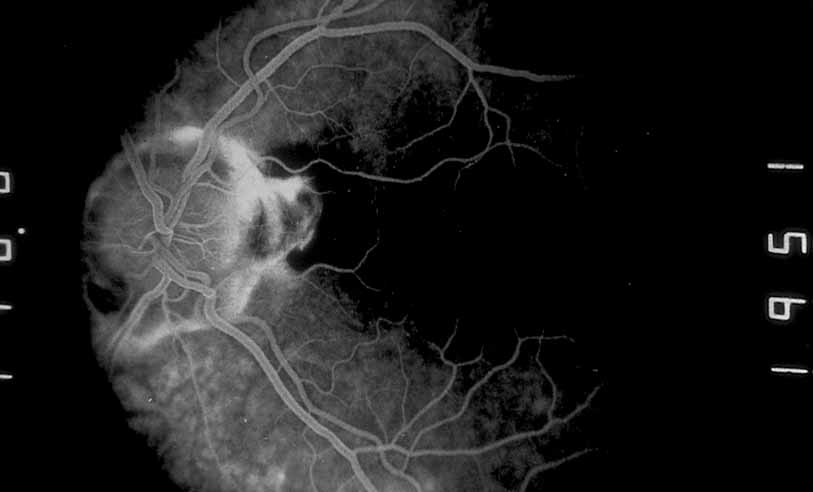

A third instance in which fluorescein angiography concentrating on the optic nerve may be helpful is in eyes with vascular engorgement of the optic nerve, especially with media opacities. Fluorescein angiography may help the clinician distinguish abnormally leaking capillaries from neovascularization. In acute multifocal hemorrhagic retinal vasculitis, optic nerve involvement is common in the early stages of the disease, 47 with optic nerve disc neovascularization seen later (see Figs. 10, 11, 12, and 13). Another fluorescein angiographic clue to the distinction between optic disc vessel engorgement and true neovascularization is the presence of associated large zones of retinal capillary nonperfusion such as those seen in sarcoidosis (see Figs. 14 and 15),34–40 acute multifocal hemorrhagic retinal vasculitis (see Figs. 10 and 11),47 or Eale disease (see Figs. 16 and 17).48–52

Fig. 10 Acute multifocal hemorrhagic retinal vasculitis. A middle-aged man presented with the picture of multiple branch vein obstructions and low-grade intraocular inflammation.

Fig. 11 Acute multifocal hemorrhagic retinal vasculitis. Fluorescein angiogram confirms the presence of associated retinal capillary non-perfusion without neovascularization at the onset of the disease.

Fig. 12 Acute multifocal hemorrhagic retinal vasculitis. The patient later developed disk neovascularization with vitreous hemorrhage. Note the areas of neovascular leakage from the optic nerve.

Fig. 13 Acute multifocal hemorrhagic retinal vasculitis. The patient underwent scatter laser photocoagulation to the zones of retinal capillary nonperfusion, which resulted in regression of the neovascularization.